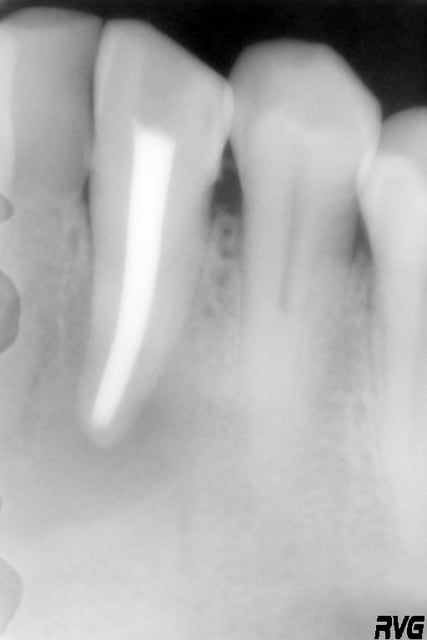

Un patient, 60 ans, présente une image apicale au niveau de 33, avec une fenestration ; tiers apical de la racine visible via la fenestration.

Ci joint, la radio de la 33 après le curetage par le stomato.

la radio pas top mais on l'a, radiologiquement correcte on dirait